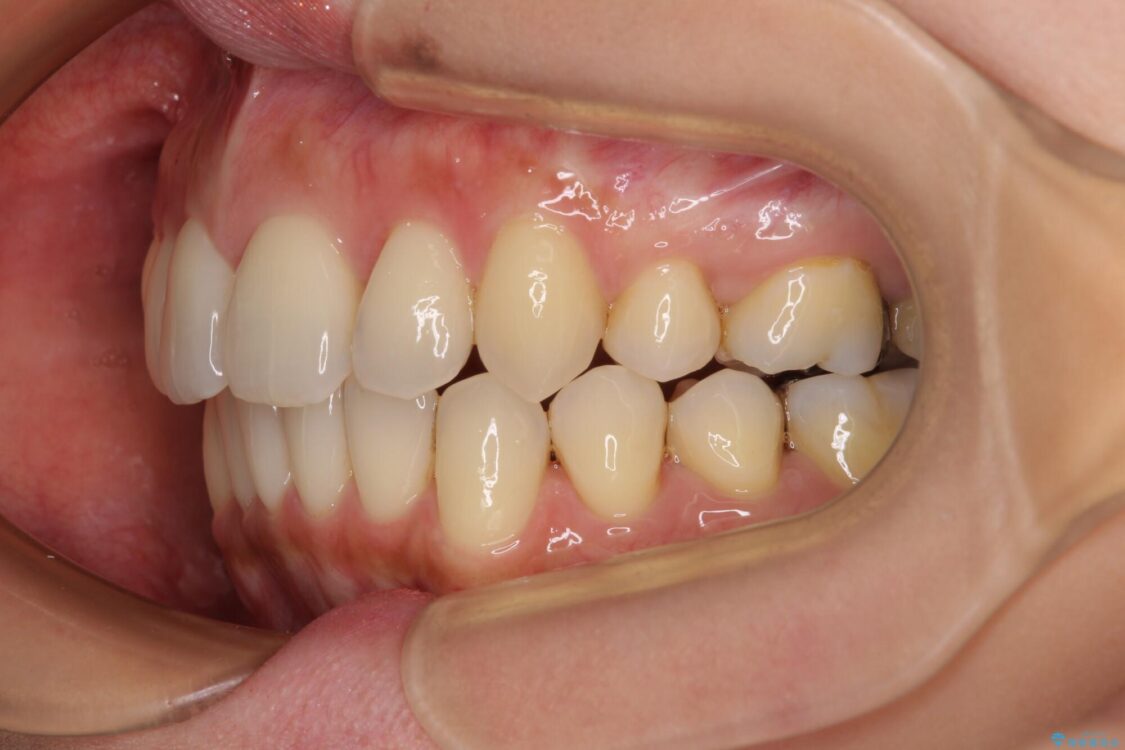

上の前歯の突出感を気にして来院された患者様です。

目立たない装置を希望とのことで、上顎左右第一小臼歯を抜歯し、インビザラインにて矯正治療を行うこととしました。

治療前

• 上顎前歯の突出を軽減 インビザラインによる抜歯矯正 治療前画像